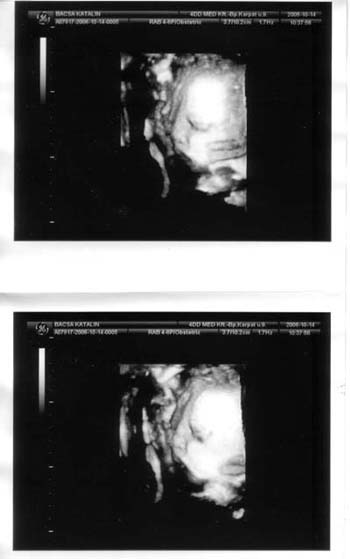

Nagyon édes a babád az uh-os képen!!!